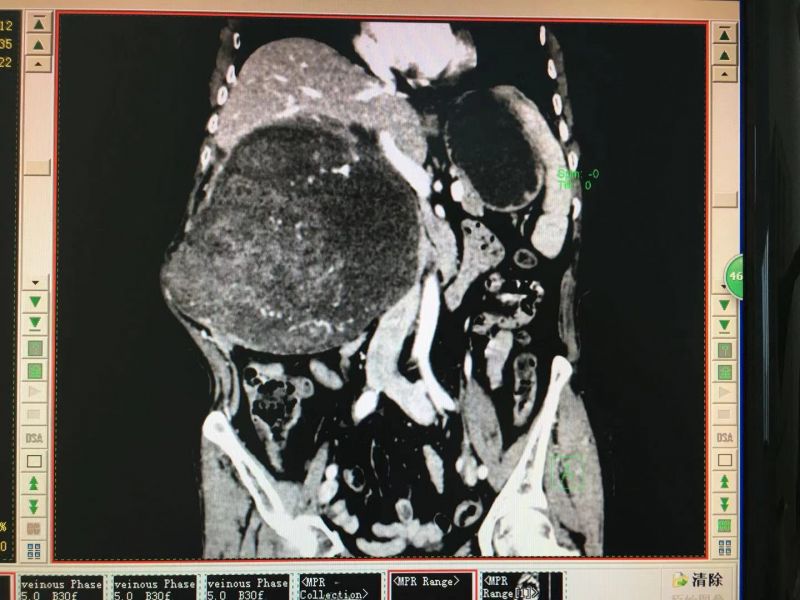

入院以后进一步完善CT检查,提示“腹腔内巨大实性肿块,直径约大小25cm,边界不清楚,周围脏器受挤压变性,肿块内有多条增粗的血管”。 完善检查后,科内对宋老太太的病情及手术方案进行了讨论,患者具有“高龄、营养状况差、肿块来源、性质不明、肿瘤周围组织器官是受压或是侵犯,尚不明确”等特点,必须做好联合器官组织切除重建的准备,手术风险和难度术前没办法判断。但肝胆外科一病区的医务人员有信心、有能力完成该类型手术,在和患者及家属充分沟通后,决定为其实施“剖腹探查术(备腹腔巨大肿瘤切除术)”,完善术前准备。

术前影像资料